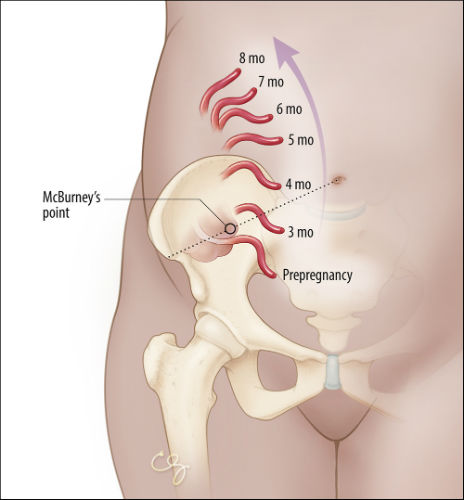

Women’s Appendix Human Body – 3ds human female anatomy

Abdominal Pain in Early Pregnancy | PSNet